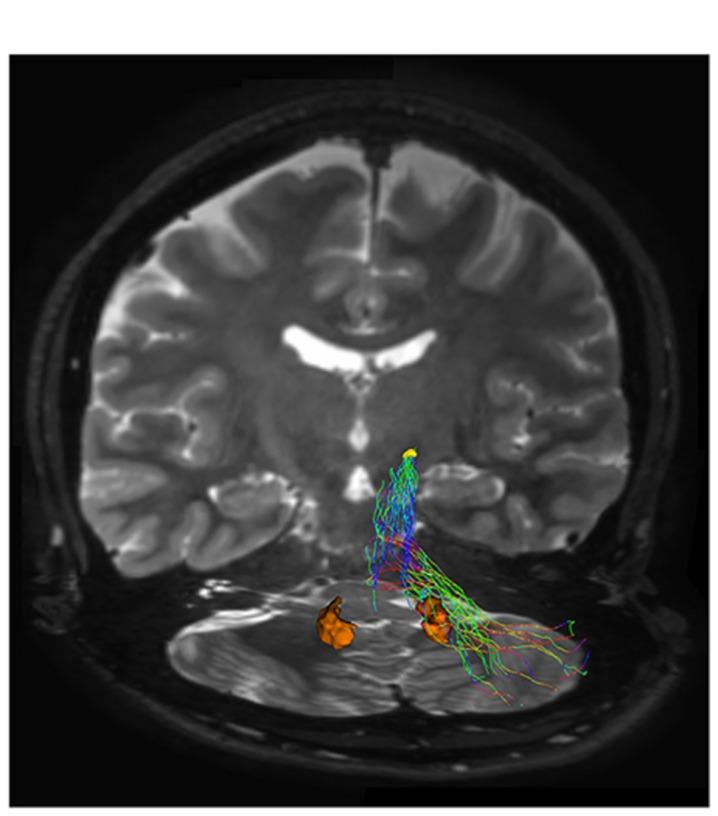

The connections between the cerebellum and basal ganglia were assumed to occur at the level of neocortex. However evidences from animal data have challenged this old perspective showing extensive subcortical pathways linking the cerebellum with the basal ganglia. Here we tested the hypothesis if these connections also exist between the cerebellum and basal ganglia in the human brain by using diffusion magnetic resonance imaging and tractography. Fifteen healthy subjects were analyzed by using constrained spherical deconvolution technique obtained with a 3T magnetic resonance imaging scanner. We found extensive connections running between the subthalamic nucleus and cerebellar cortex and, as novel result, we demonstrated a direct route linking the dentate nucleus to the internal globus pallidus as well as to the substantia nigra. These findings may open a new scenario on the interpretation of basal ganglia disorders.

小脑与基底神经节之间的连接曾被认为发生在新皮层水平。然而,动物数据的证据对这一旧观点提出了挑战,显示出连接小脑与基底神经节的广泛皮质下通路。在这里,我们通过使用扩散磁共振成像和纤维束成像技术,测试了人类大脑中小脑与基底神经节之间是否也存在这些连接的假设。对15名健康受试者使用3T磁共振成像扫描仪获得的约束球形反卷积技术进行分析。我们发现丘脑底核与小脑皮质之间存在广泛连接,并且作为新的结果,我们证明了一条将齿状核与苍白球内部以及黑质相连的直接路径。这些发现可能为基底神经节疾病的解释开辟一个新的局面。